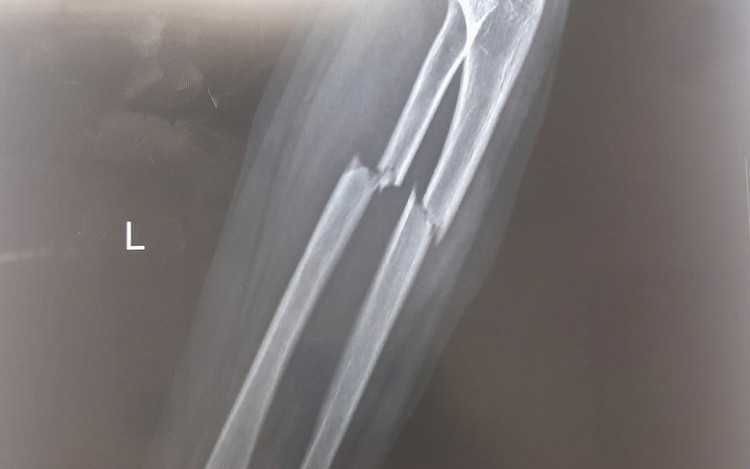

nga-xe-dap-1.jpg

Phẫu thuật kết hợp xương cố định xương gãy, phục hồi vận động sớm - Ảnh BVCC

Sau hơn 1 giờ phẫu thuật, dưới sự hỗ trợ của hệ thống máy C-arm, ê-kíp phẫu thuật tiến hành nắn chỉnh trục xương giúp đưa hai đầu xương gãy và mảnh xương di lệch về đúng vị trí giải phẫu, khôi phục chiều dài và chức năng sấp, ngửa của cẳng tay.

Sau đó, phẫu thuật viên đặt nẹp vít cố định nhằm giữ vững hai đoạn xương, tạo điều kiện cho quá trình liền xương diễn ra đúng vị trí giải phẫu, tránh nguy cơ sai lệch hoặc biến dạng. Toàn bộ quá trình phẫu thuật được thực hiện qua một đường mổ nhỏ ở phía trước. Chỉ với một đường tiếp cận này, phẫu thuật viên có thể nắn chỉnh và cố định đồng thời cả hai xương gãy, giúp giảm tổn thương phần mềm, hạn chế mất máu và giảm đau sau mổ cho bệnh nhi.